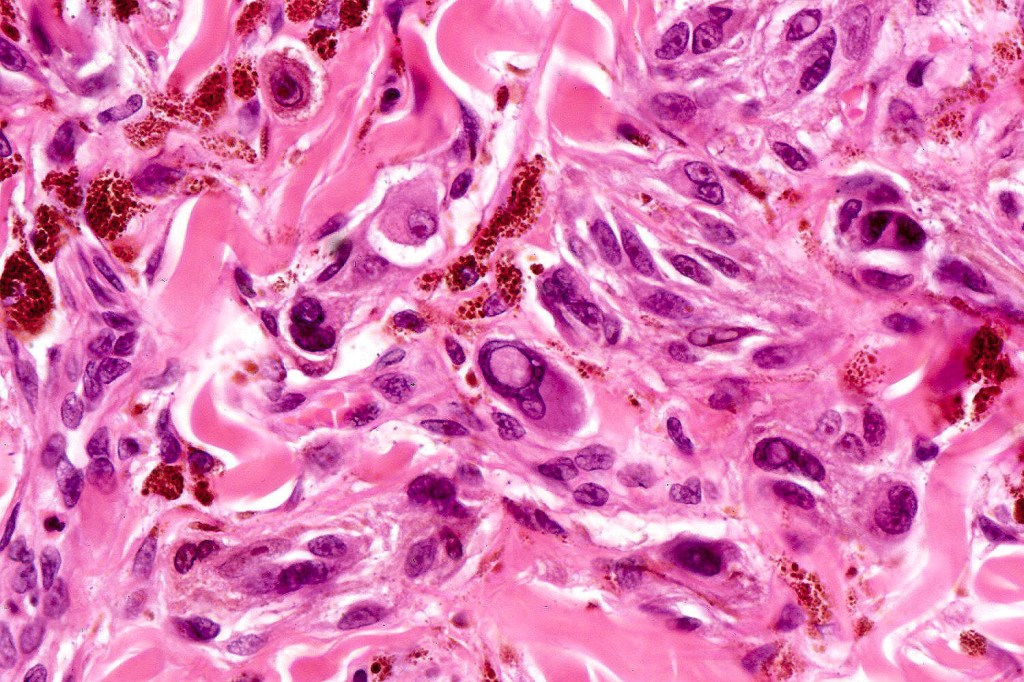

Cellular blue nevus

Histological features

•Most characteristic is the dumbbell silhouette although a plague morphology may also be encountered

•Combined nevus variant

•Admixture of spindle cells, pigmented bipolar or dendritic cells & melanophages

•Cytoplasm is pale and nuclei are small with inconspicuous nucleoli

•An alveolar pattern is characteristic particularly with clear cell nodules

•Mitoses are typically very sparse or absent

•No atypical mitoses

•No Necrosis or lymphovascular invasion

•Multinucleate giant cells sometimes present

•Stromal fibrosis, myxoid change, vascular hyalinization with cyst formation are often seen

•Some tumors are composed spindle cells in a fascicular or neuronevoid pattern

•Perineural involvement may be seen

•Balloon cell change

•Desmoplastic variant

•Hypopigmented variant